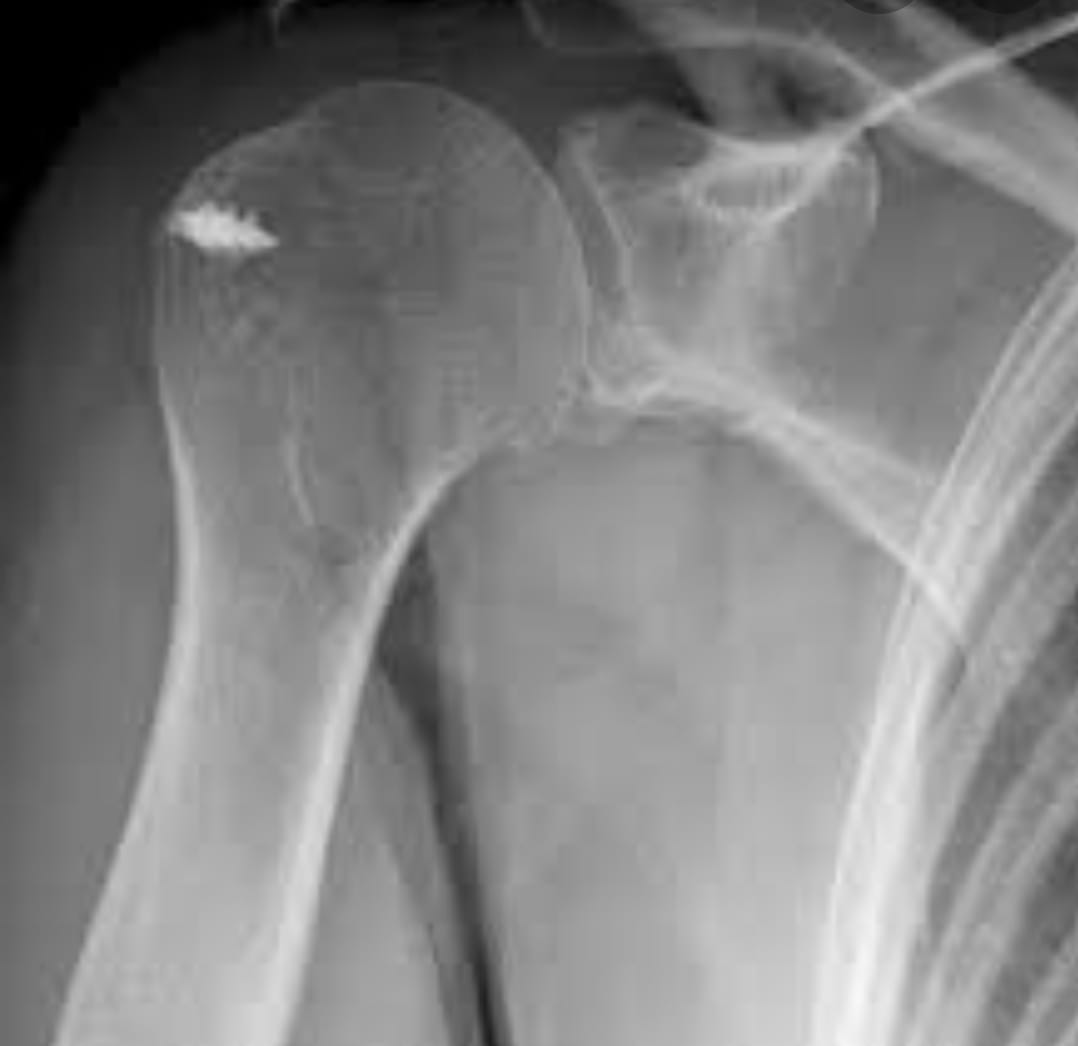

Shoulder replacement surgery is a procedure where damaged parts of the shoulder joint are replaced with artificial components to relieve pain and restore function.

Rotator cuff and ligament injuries involve damage to the muscles, tendons, and ligaments that stabilize joints. Dr. Mayank offers comprehensive evaluation and treatment options.